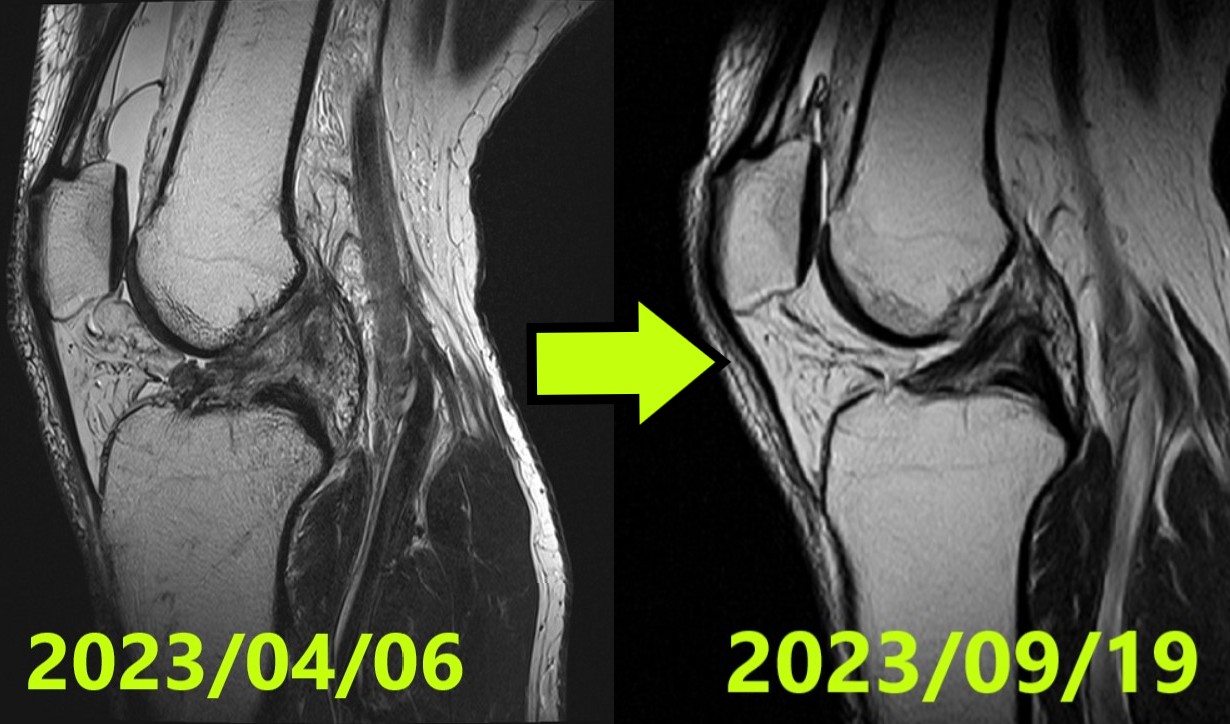

ACL Tear Natural Healing Case Report #50Case 50 | Natural Healing of Complete ACL Rupture: From Severe Ihara Type IV to Perfect Regeneration (ACLOAS Grade 0)